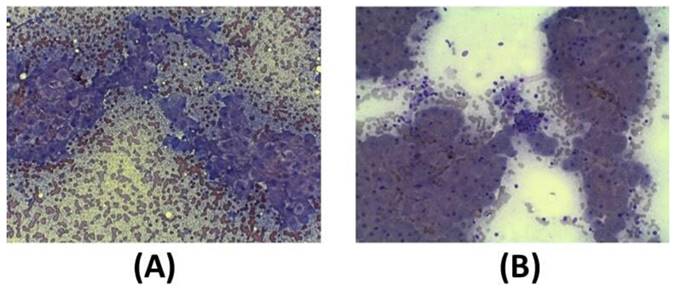

In addition to clinical sign, cytological analysis in a small (12) group of dogs before the first exosome injections and 30 days after the second injection was performed. As reported in the guidelines, the key features of liver biopsy specimen interpretation include evaluation of inflammation (granulomatous, neutrophilic, lymphocytic, suppurative inflammation). Moreover, it is mandatory to analyze the extent and distribution of cell death (i.e., individual, massive, multifocal, centrilobular, and periportal cells), characterized by vacuolar shift. Often, fibrosis of the connective tissue is also present as septa formation and nodular regeneration of hepatocytes. Before exosome injections, hepatocytes show a round central nucleus, and the presence of inflammation process is demonstrated by the presence of neutrophils, small and medium activated lymphocytes, and foamy macrophages (Figure 6A). After the second injection of exosomes (after 30 days), cytological images show that liver inflammation is declined, as well as the presence of spindle cells; furthermore, no sign of fibrosis is evident (Figure 6B).

Figure 6

Diff-quick stain of cytological samples before and 30 days after the second exosome injection after 30 days. (A) Before exosome treatment, inflammatory processes are occurring with foamy macrophages and hepatic debris; red cells are also visible. (B) After exosome treatment, fibrosis and inflammation are strongly reduced.

Nanotheranostics Image